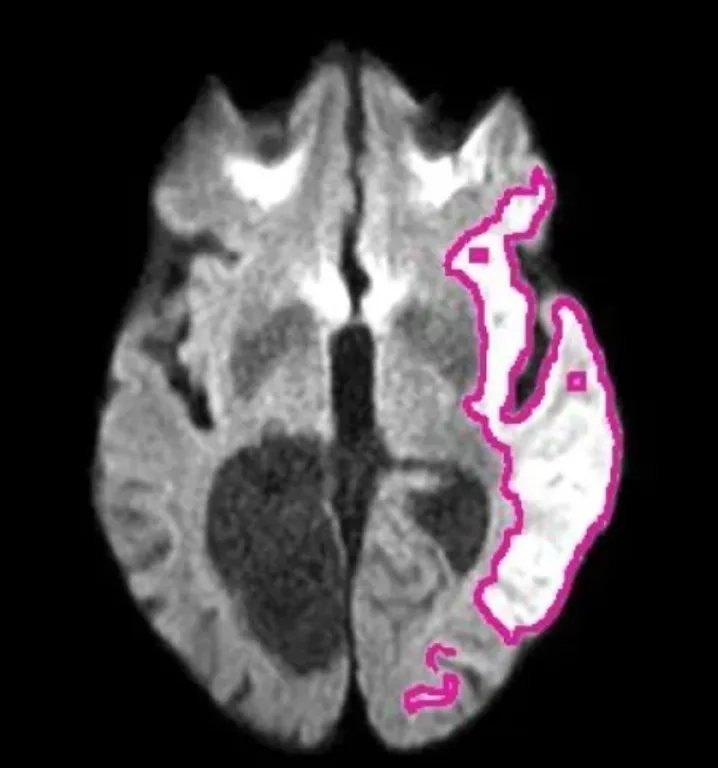

DeepISLES se basa en Inteligencia Artificial (IA) y fue validado en el exigente desafío internacional ISLES’22, así como en imágenes de resonancia magnética provenientes de distintos hospitales del mundo. Logró mejoras de hasta +7,4 % en el índice Dice y +12,6 % en el F1-score frente a métodos previos, manteniendo su rendimiento incluso con imágenes, lesiones y pacientes muy diversos.

Uno de los hitos del desarrollo fue un “pseudo Turing test”: expertos en neurorradiología recibieron imágenes con lesiones delineadas automáticamente por DeepISLES y otras hechas manualmente por colegas, sin informarles cuáles eran de cada origen. El resultado sorprendió: los especialistas prefirieron en mayor medida las segmentaciones generadas por el algoritmo que las realizadas por otros expertos humanos.

El sistema, disponible en código abierto, puede integrarse en hospitales y centros de diagnóstico para analizar resonancias de forma casi instantánea, señalando con precisión la zona del cerebro afectada por la falta de irrigación. En la práctica, esto podría acortar drásticamente los tiempos de diagnóstico en guardias y ayudar a estandarizar la calidad de atención en todo el mundo.